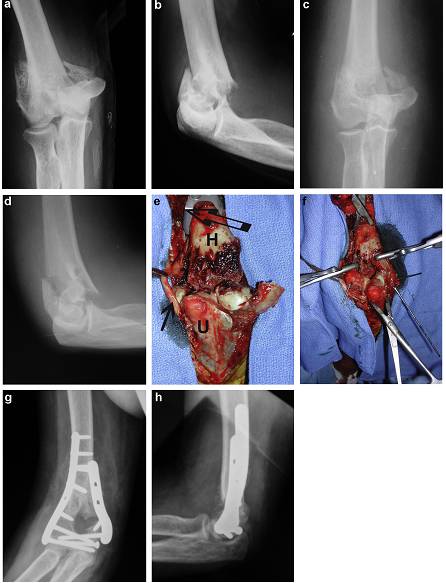

CT扫描对于部分远侧骨折尤其重要,此类骨折骨折块常处于重叠状。CT三维重建可很好的显示骨折块的形态和位置,有利于确定相应的手术入路(图2)。相对于X线,对于所有类型骨折,CT均可发现更多骨折块。相对于2D轴位片,3D重建的诊断准确性在观察者组间重复性更高。Doornberg等认为CT扫描和重建是制定术前计划的唯一有效影像学检查。

图2,C型骨折,X线检查和CT重建。